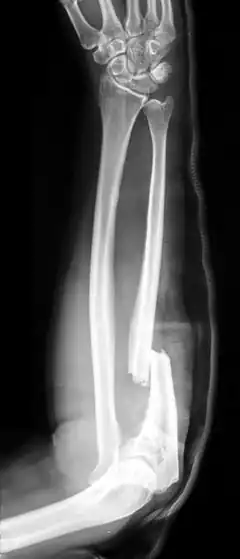

- Galeazzi fracture - not a fracture of the ulna but a displaced fracture of the radius accompanied by a dislocation of the ulna at the wrist, where the radius and ulna come together.[2]

Galeazzi facture (displaced fracture of the radius)